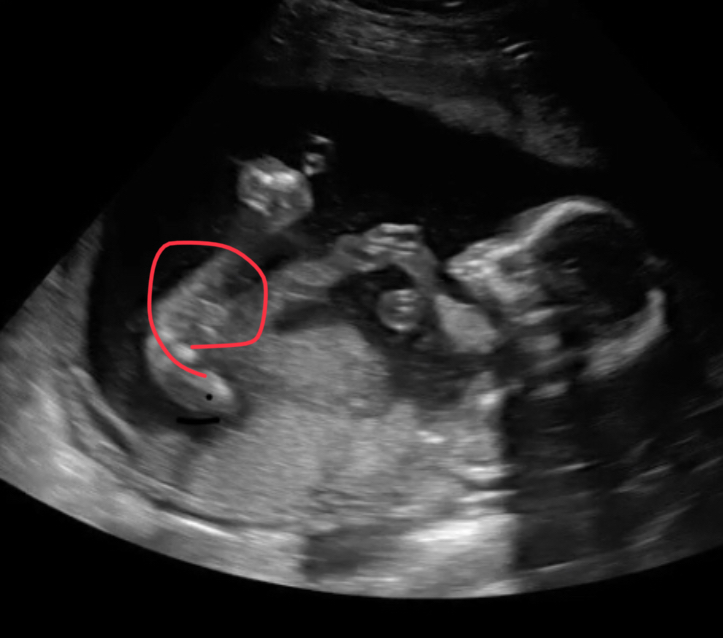

I think it looks like a willy in the ultrasound, but looking for opinions. Thanks!

Can't guess on that, do you have any others?